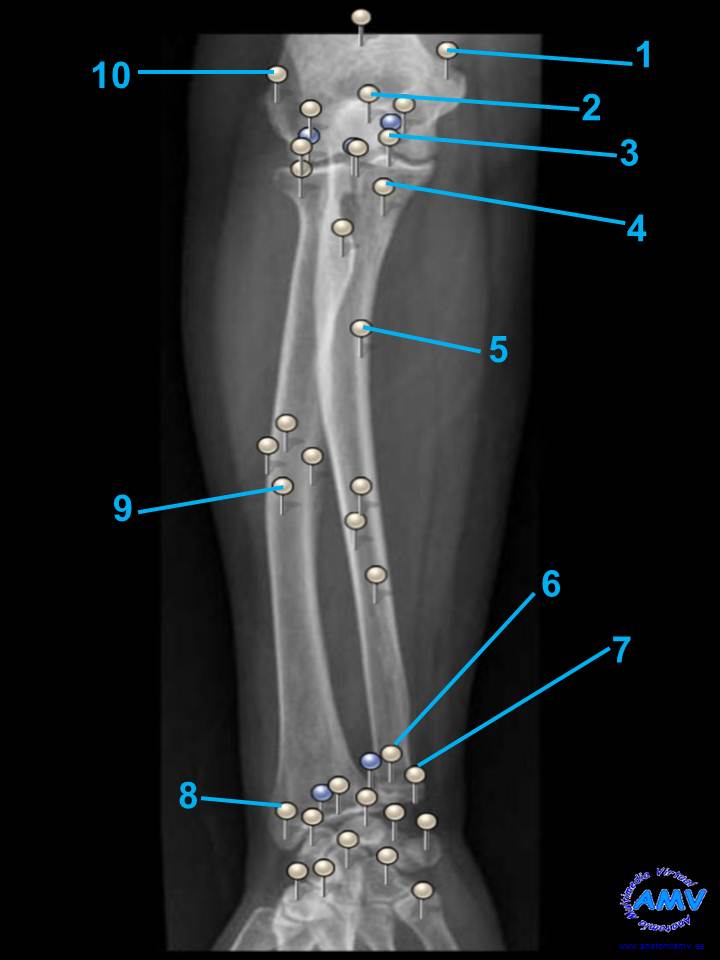

Radiografía del Antebrazo

rx_ms_09.jpgIndique que estructura se señala con el número correspondiente:

El nº 1 señala .

El nº 2 señala .

El nº 3 señala .

El nº 4 señala .

El nº 5 señala .

El nº 6 señala .

El nº 7 señala .

El nº 8 señala .

El nº 9 señala .

El nº 10 señala .